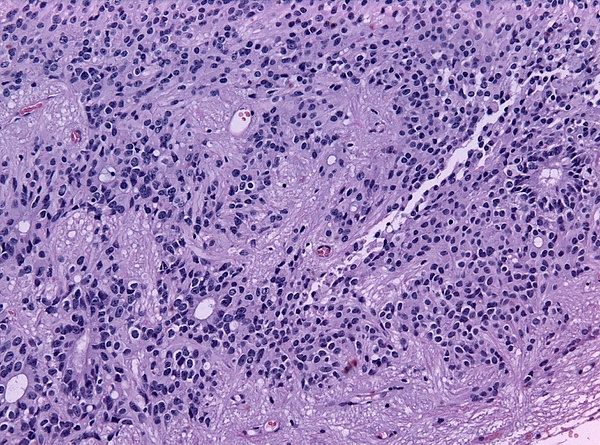

Псевдорозетки Гомера Райта является одним из видов псевдорозеток, в котором дифференцированные клетки опухолей окружают нейропиль.[7] Примерами опухолей, содержащих эти розетки, являются нейробластома, медуллобластома, пинеалобластома и примитивные нейроэктодермальные опухоли кости. Розетки Гомера Райта являются «псевдо» в том смысле, что они не настоящие розетки. Настоящие розетки — это розетки Флекснера-Винтерштайнера, которые содержат пустой просвет. Розетки Гомера-Райта содержат большое количество фибриллярного материала. Они названы в честь Джеймса Гомера Райта.